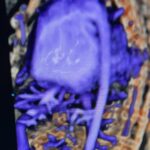

L’ecografia tridimensionale (3 D) e tridimensionale in tempo reale (4D) viene utilizzata nel nostro centro di routine in tutti gli esami e ad ogni epoca gestazionale.

La caratteristica della tecnologia tridimensionale consiste nel fatto che non si lavora su un piano ma su un volume. Pertanto è possibile non solo, esaminare un determinato distretto nelle tre dimensioni, ma di manipolare sui tre piani il volume immagazzinato, consentendo di mettere in evidenza strutture anatomiche altrimenti difficilmente evidenziabili. Pertanto il 3D e il 4D non viene utilizzato esclusivamente per visualizzare il visino del feto* e le parti superficiali come le mani e i piedi ma per studiare il cervello (neurosonografia)**, l’apparato scheletrico *** e quello cardiocircolatorio****.